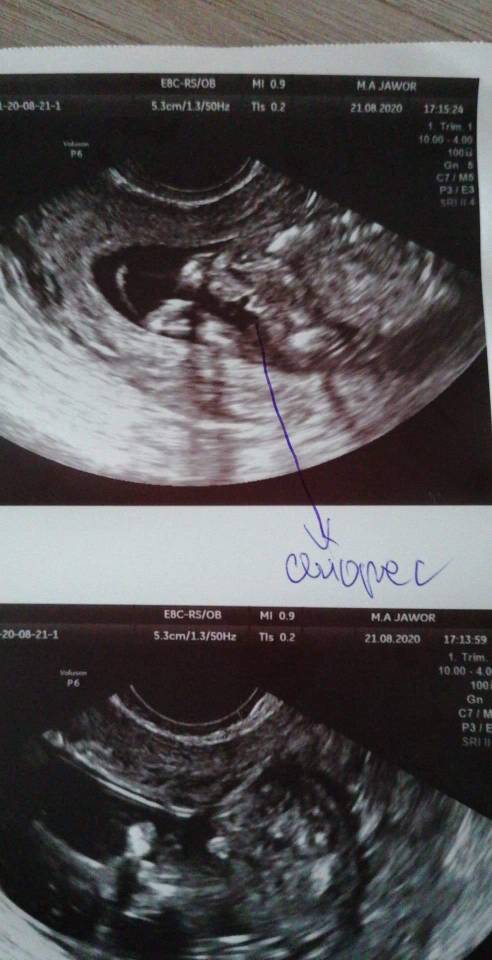

Chlopiec?

Dziewczy moja doktorka mowi ze to milion procent chlopak. Ale wole jeszcze was spytac co myslicie :) 16tc

Slabo widac, ale u mnie takie cos bylo w 17 tygodniu (takie odstajace cos ;) )i doktor powiedziala ze na 70% chlopak dopiero na polowkowych potwierdzili. Nie kieruj sie raczej moja ocena, bo lekarz krecac glowica widzi lepiej na dany moment co tam miedzy nozkami dzidzia ma :)

Ma coś Maluch między nóżkami :) ale ( nie wiem w którym jesteś tygodniu) poczekałabym aby się upewnić do 5-6 miesiąca. Przynajmniej my mamy takie podejście. Lekarze często mówią, że 100% a potem się okazuję, że klops no ale to przecież nie ich problem jak ktoś zrobi wyprawkę pod inną płeć :D